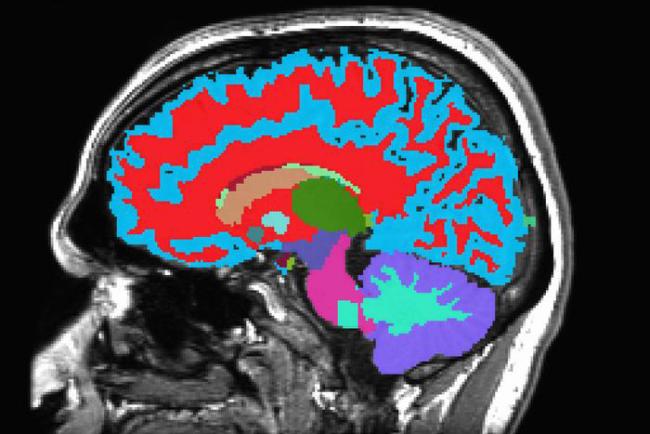

La mayoría de los participantes del estudio también realizaron un escáner de tomografía de resonancia magnética (MRI, por sus siglas en inglés) a los 45 años de edad. En el nuevo estudio, el equipo combinó los puntajes de la Velocidad del Envejecimiento con los datos del escáner MRI. Desarrollaron una nueva medición de envejecimiento, llamado Dunedin-PACNI, basada sólo en los escáneres cerebrales. Entonces probaron la nueva herramienta con información recolectada de miles de personas de otros estudios.